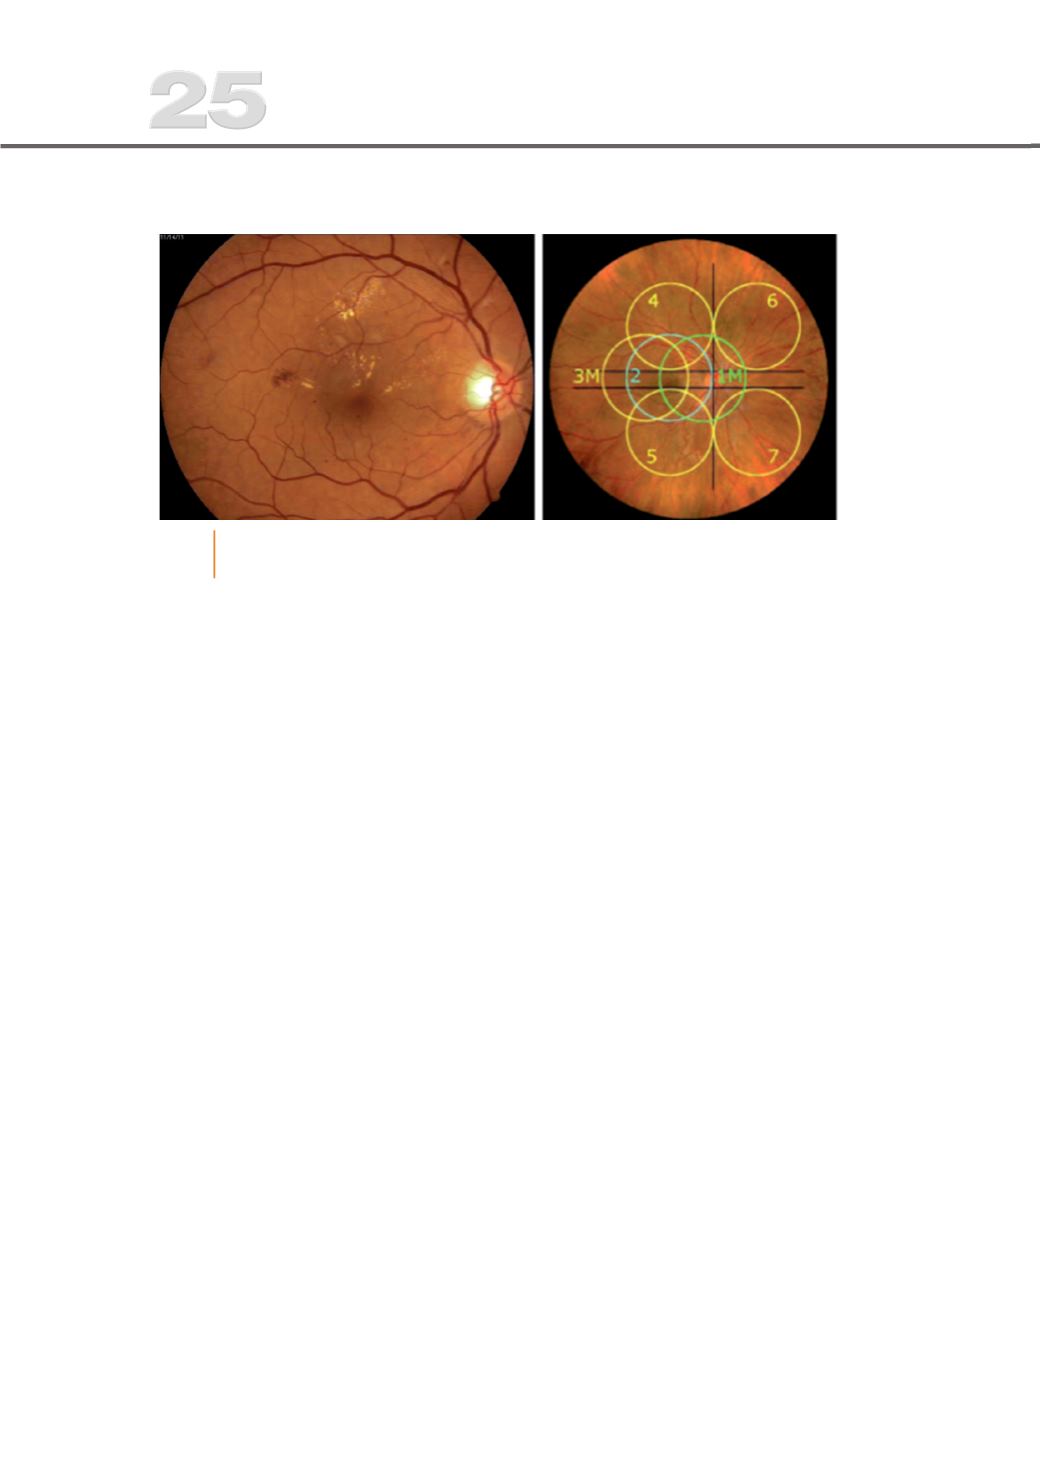

Fig. 1

Retinogra%a de doente com lesões de RD não proliferativa (à esquerda) e

representação de 7 campos ETDRS

standard

– olho direito (à direita).